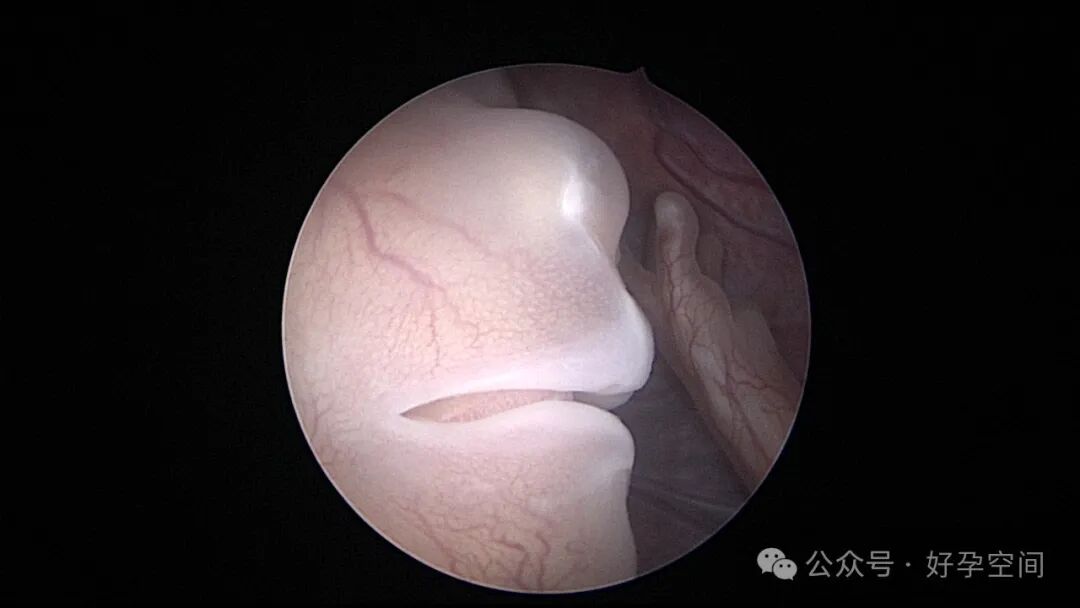

宫腔镜下的胚胎图解

宫腔镜下的胎儿(自妊娠第11周,即受精第9周起称为胎儿)